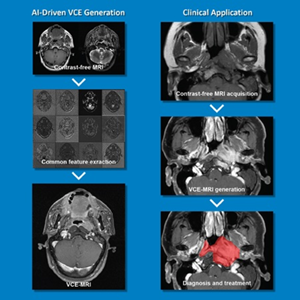

Prof. CAI Jing, Management Committee Member of the Research Institute for Smart Ageing (RISA), Associate Dean of the Faculty of Health and Social Sciences and Professor in the Department of Health Technology and Informatics, developed a Contrast-Free Virtual Enhancement MRI System that revolutionises the precision of tumour treatment by providing high-resolution imaging without the use of contrast agents.

The system leverages advanced algorithms and innovative imaging techniques to precisely visualise tumours, thus facilitating treatment planning and accurate monitoring. The system offers advantages in terms of patient safety, cost-effectiveness and enhanced accuracy. It eliminates the use of contrast agents, thereby prioritising patient well-being and minimising potential health and safety risks in tumour detection and treatment. The enhanced accuracy of tumour visualisation improves treatment outcomes and patient care.

The novel system sets a new standard for non-invasive, safe and highly accurate tumour imaging. It advances the field of precision medicine and improves patient outcomes in the fight against cancer. The system has been patented to MedVision Limited, a PolyU start-up, for distribution.